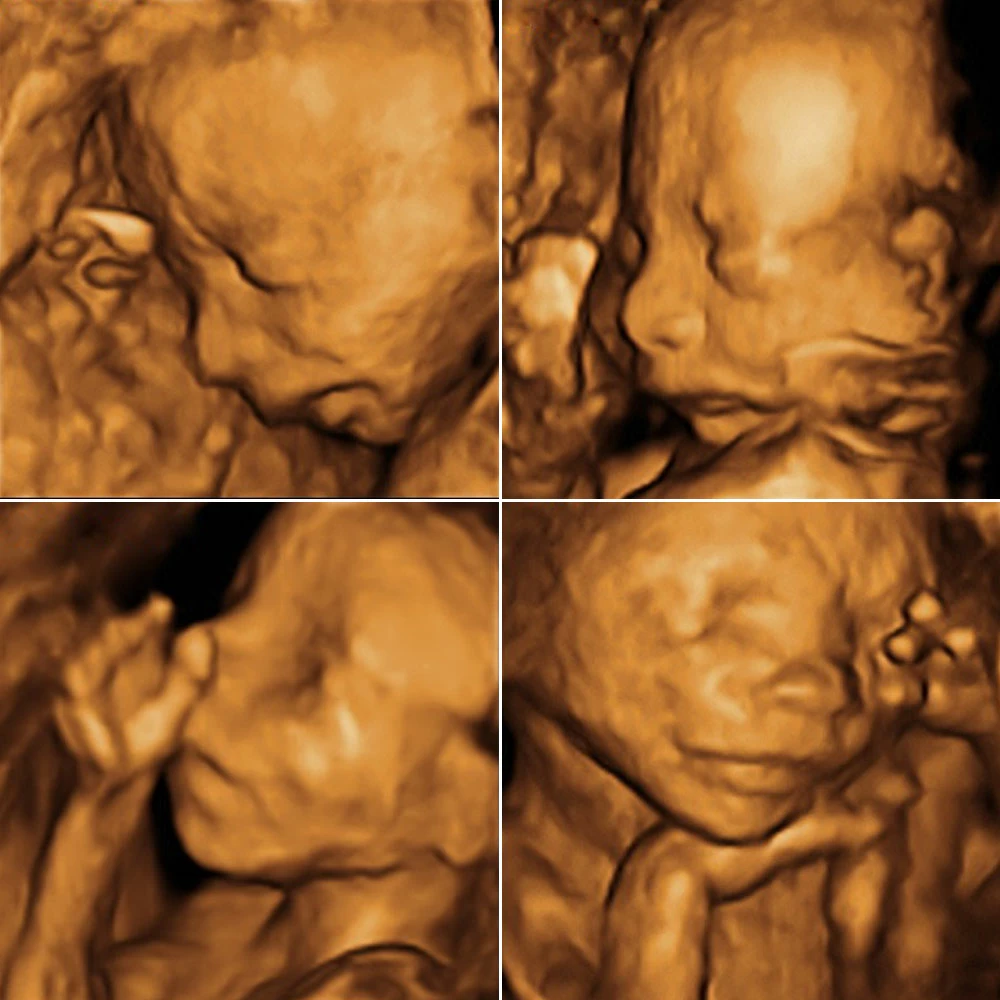

Самая точная УЗ-диагностика с помощью аппаратов премиум-серии